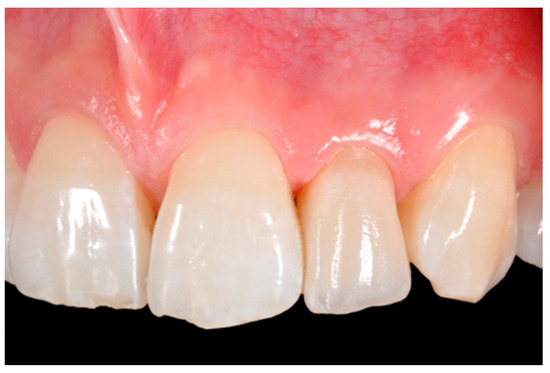

A 42-year old woman presented to the clinic with esthetic concerns related to her upper left lateral incisor (Figure 20). Pre-operative x-rays showed periapical lesion that required retreatment. After retreatment (Figure 21) a treatment plan was proposed to the patient. The ideal treatment would have involved an orthodontic therapy to gain back lost space in mesial portion. The patient decided not to consider an orthodontic treatment and accepted just the restorative proposal (Class IV restoration). Considered the sufficient amount of ferrule no post was applied [16]. Shade was selected as described in previous case, using the button-try technique [14]. After isolation with rubber dam, preparation (Figure 22) and adhesion (Clearfil SE, Kuraray Noritake Dental, Tokyo, Japan), composite frame was completed (Clearfil Majesty ES-2, A1D, Kuraray Noritake Dental, Tokyo, Japan) with silicone index and interproximal transparent mylar matrices (Figure 23). Interproximal walls were considered too thick; therefore, they were reduced (Figure 24) using diamond bur as described in Section 2.1.2. This allowed the internal dentinal body to have the correct volume (Figure 25) and therefore to respect ideal opacity/translucency ratios. Restoration was therefore completed adding enamel layer (Clearfil Majesty ES-2, A1E, Kuraray Noritake Dental, Tokyo, Japan) and performing finishing and polishing procedures (Figure 26 and Figure 27) as described in previous clinical case. The restoration shows good integration 6 months post-operative (Figure 28 and Figure 29).

Figure 28.

Six-months post-operative. Reprinted from Restauri diretti nei settori anteriori, G. Paolone, S. Scolavino, © 2021, with permission from Quintessence Publishing Italy.